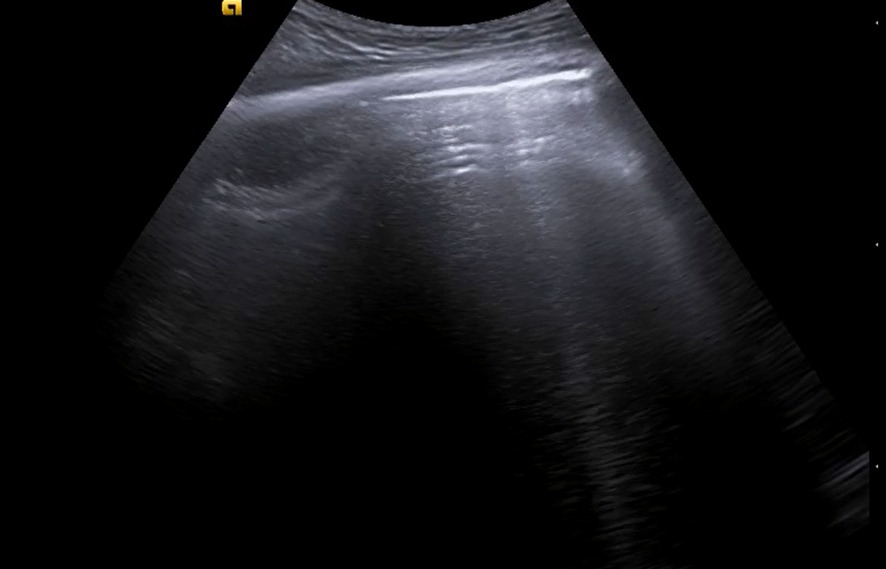

Realizamos ecografía clínica en la consulta objetivando un gran derrame pleural loculado de contenido ecogénico, con finos septos interiores y signo de la espina. Destaca que en el parénquima pulmonar no se observan datos de atelectasia, broncograma aéreo, consolidación ni hepatización, y apenas líneas B.